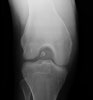

관절내 유리체(Intra-articular loose body)

X-ray : Intra-articular loose body